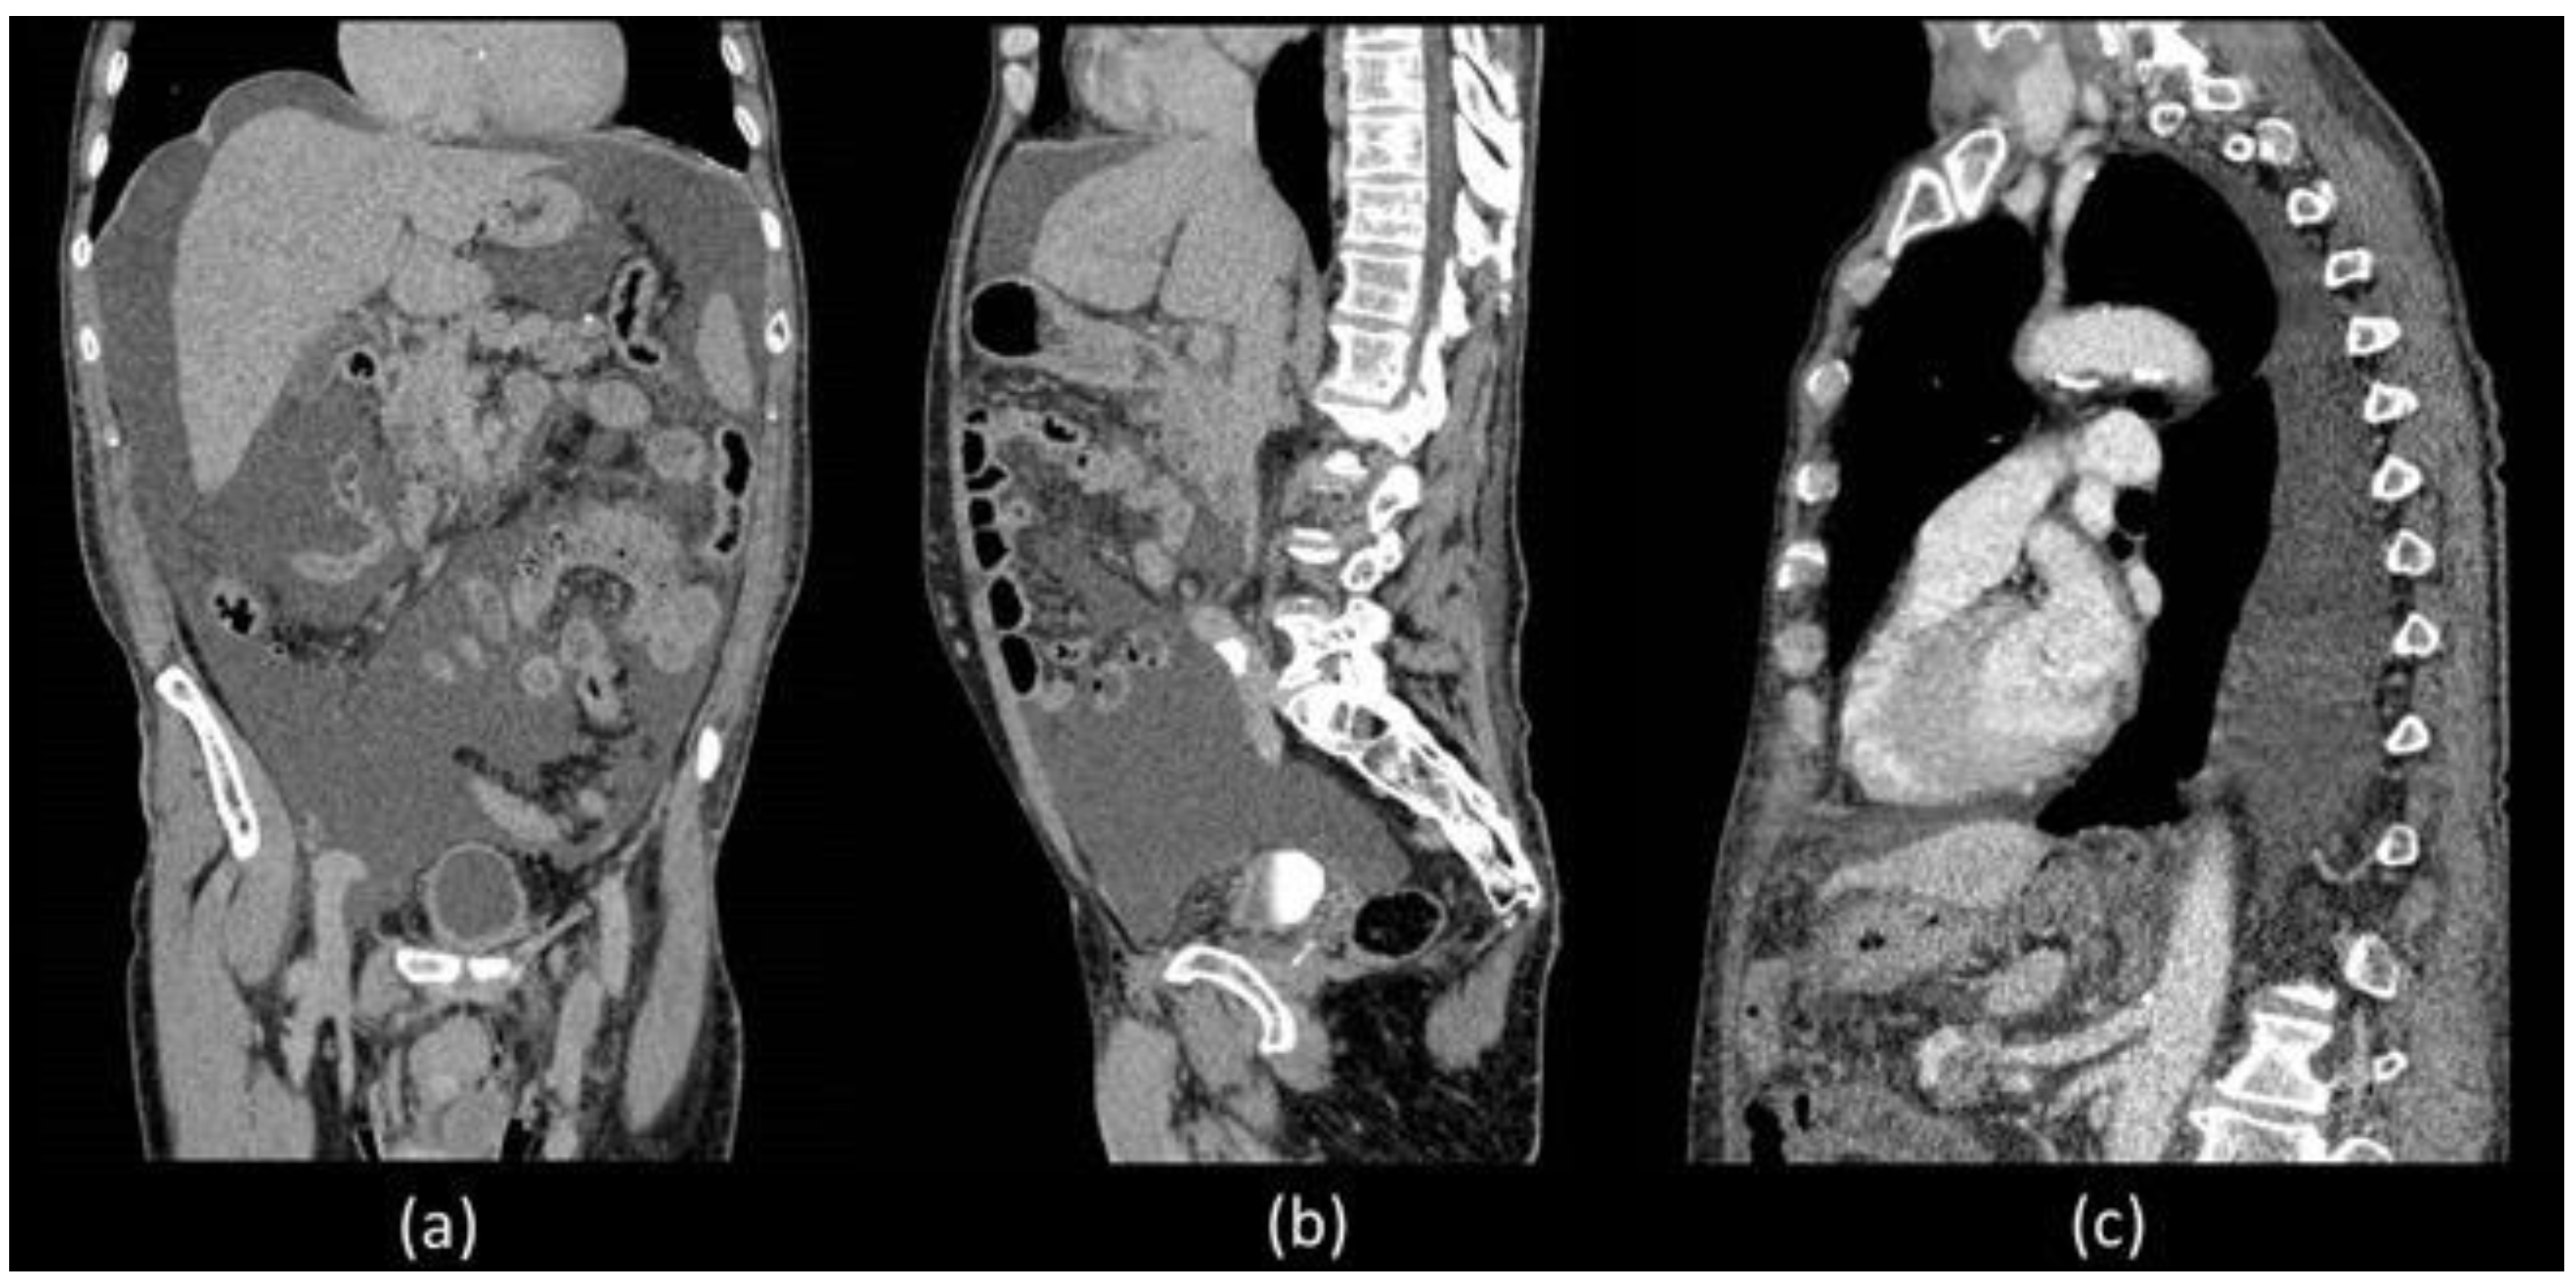

Unfortunately, he was readmitted 7 days later with abdominal distension and dyspnoea. During hospitalization, thorax and abdominal contrast-enhanced CT was performed which confirmed a massive ascites and described the presence of left pleural effusion without the presence of liver diseases (Figure 1).

Coronal (a) and sagittal (b) abdominal CECT showed massive ascites in supra and inframesocolic recesses. Non-hepatic diseases were recorded. (c) Sagittal thorax CECT demonstrated left pleural effusion.

CT is the imaging modality of choice to evaluate intraperitoneal fluid accumulations and may be particularly helpful in the setting of postoperative causes of CA to determine the extent and location of possible injuries [2,11]. In our patient, both abdominal and thoracic CT were performed which demonstrated the presence of a significant amount of CA distributed throughout the peritoneal cavity but also the presence of pleural effusion, on whose etiology was not possible to express considering that the CT density of chylous resembles that of water and is indistinguishable from simple effusion. Furthermore, no alterations attributable to post-surgical damage were identified. Abdominal radiological imaging can include MR, which is not specific to CA but can be useful in identifying intra-abdominal masses, lymph node alterations and liver evaluation [6]. In our patient, there was no imaging evidence of liver, spleen or kidney disease responsible for CA.